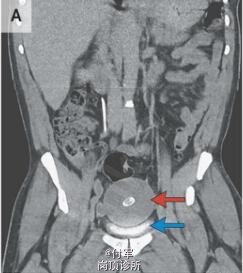

体格检查和实验室检查无异常。腹部和骨盆CT显示有一个直径为8.5cm长的肿块,伴有中心钙化(图A,红色箭头),在膀胱上方并压迫膀胱(图A,蓝色箭头)。 腹腔镜探查显示一个游离、光滑、坚硬且有弹性,10cm×9.5cm×7.5cm,重220克的肿块(图B和图C)。 切片标本包含多层,绿色墨水用来描绘切片边缘(D图)。组织学上,该肿块主要包含非细胞、分层的纤维组织,标本中心包含蛋白样组织伴有纤维样坏死,周围一圈钙化。